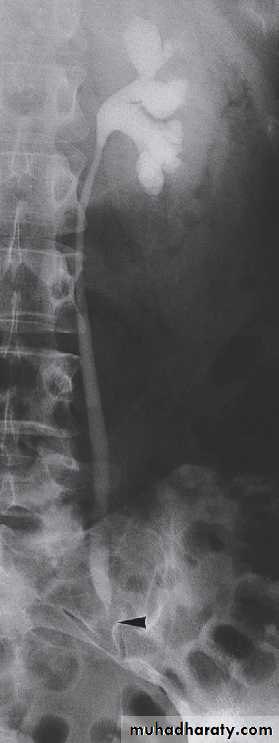

Retrograde and antegrade pyelographyThe techniques of retrograde and antegrade pyelography (the term pyelography means demonstrating the pelvicaliceal system and ureters) involve direct injection of contrast material into the pelvicaliceal system or ureters through catheters placed via cystoscopy (retrograde pyelography) or percutaneously into the kidney via the loin (antegrade pyelography).

The indications are limited to those situationswhere the information cannot be achieved by less invasive means, e.g. IVU, CT or MRI to confirm a possible transitional cell carcinoma in the renal pelvis or ureter.